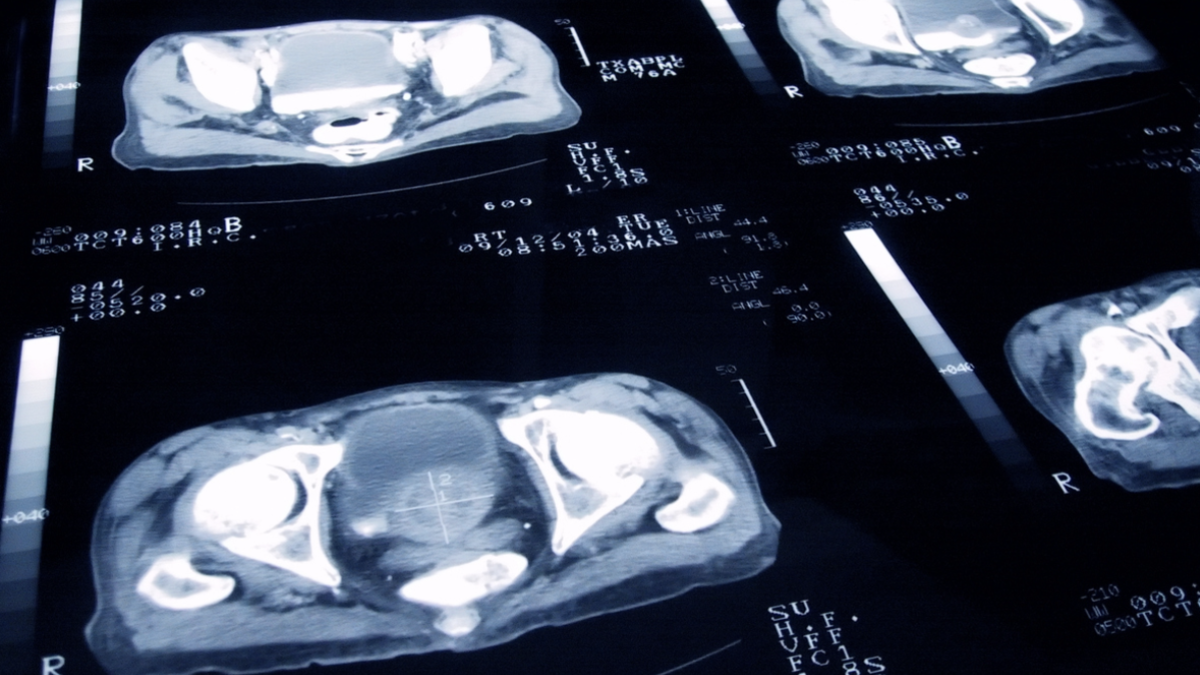

Erkeklerin sessiz hikâyesi: Prostat hastalığı

Sağlık çoğu zaman konuşulmayanı konuşmakla başlar. Özellikle erkek sağlığı konusunda bazı meseleler uzun yıllar saklanır. Prostat hastalıkları tam da bu noktada ortaya çıkar. Prostat, erkeklerin yaşam kalitesini ciddi şekilde etkiliyor.

Erkeklerde mesanenin hemen alt kısmında bulunan ve idrar yolunu saran küçük bez prostat olarak adlandırılıyor. Yaş ilerledikçe bu bezde büyüme görülebiliyor. Bu büyüme bazen iyi huylu bazen ise kötü huylu yani prostat kanserine dönüşebiliyor.